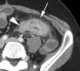

Mesenteric abscess